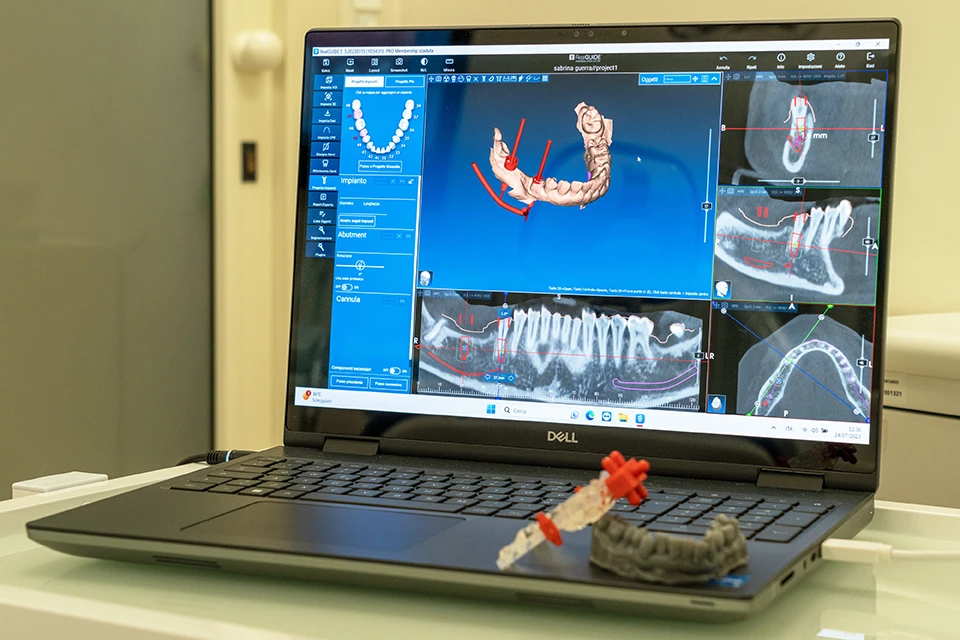

Programma Real Guide

Per quanto riguarda la chirurgia, la tecnologia ci aiuta nel progettare l’intervento implantare potendo inserire gli impianti con precisione assoluta senza tagliare né mettere punti di sutura ed eliminando il dolore post operatorio per il nostro paziente.

I relativi kit di frese atraumatiche sono rigorosamente prodotti in Italia rispettando gli standard e le più importanti certificazioni dettate dal Ministero della Salute.

Stiamo parlando di implantologia a carico immediato con l’ausilio della computer guida.

Combinando 2 file digitali, una radiografia come-beam e una scansione laser intra-orale, è possibile ricreare osso denti e gengive del paziente su un software. Dopo aver creato il paziente “digitale” sul nostro computer è possibile inserire gli impianti ossei nella posizione voluta con una precisione di 0,1 mm. In questo modo avremmo terminato l’intervento chirurgico digitalmente. Si procederà a stampare in 3D una dima, una guida che permetterà di inserire dal vivo sul paziente gli impianti senza necessità di realizzare tagli, in modo minimamente invasivo e soprattutto senza dare dolore post operatorio. Terminata questa breve fase, si applicherà la dentatura e il paziente potrà uscire con il nuovo sorriso.

In base ai differenti casi, gli impianti possono essere inseriti in modo computer guidato con la precisone e la predicibilità di 0,1 mm immediatamente dopo l’estrazione del dente o nella zona dove manca, senza ricorrere alla lama del bisturi.